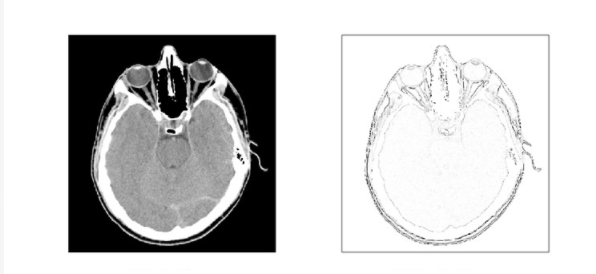

2.1 基于数学形态学的边缘检测:

数学形态学是基于积分几何和几何概论建立的关于图像形状和尺寸的研究方法,实质上是一种非线性滤波方法。数学形态学的方法应用于视觉图像的处理就是用具有一定形状、大小的结构元素去探测、度量和提取图像中对应形状,以达到对图像进行处理、分析识别的目的。在图像处理的过程中,主要使用的是二值形态学和灰度形态学。我们可以来看看这个方法对于图像轮廓的提取能力如何: